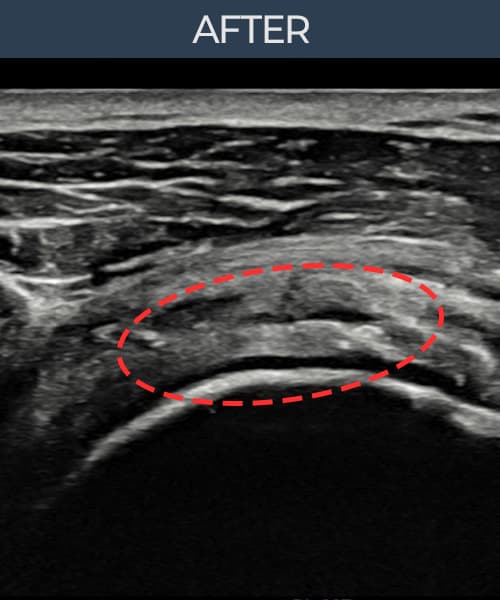

术后

术前超声确认旋转肌腱袖 关节面侧部分撕裂,冈上肌腱回声不连续伴肌腱缺损(8mm × 5mm (肌腱厚度约45%缺损))。术后超声显示撕裂部位充满再生组织,肌腱连续性恢复,回声模式正常化。

该患者持续肩痛。详细超声检查确认旋转肌腱袖 关节面侧部分撕裂(缺损:8mm × 5mm (肌腱厚度约45%缺损))。在超声引导下实施非手术缩小缝合术。术后佩戴支具约4-6周,随后进行分阶段康复锻炼。随访超声确认肌腱连续性恢复、结构稳定,患者顺利回归日常生活。